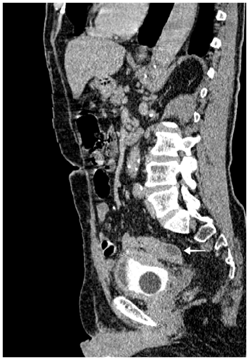

Recto-sigmoidoscopy failed to find the orifice of the fistula. Abdominopelvic computed tomography showed a circumferential thickening of the bladder wall with a posterior parietal collection of 11*16 mm in contact with the sigmoid colon. Uncomplicated colonic diverticula were also revealed (Figure 3−5).

Figure 3 Sagittal computed tomography scan showing retro vesical collection with close contact with sigmoid colon and bladder thickening its posterior wall. (Arrow)